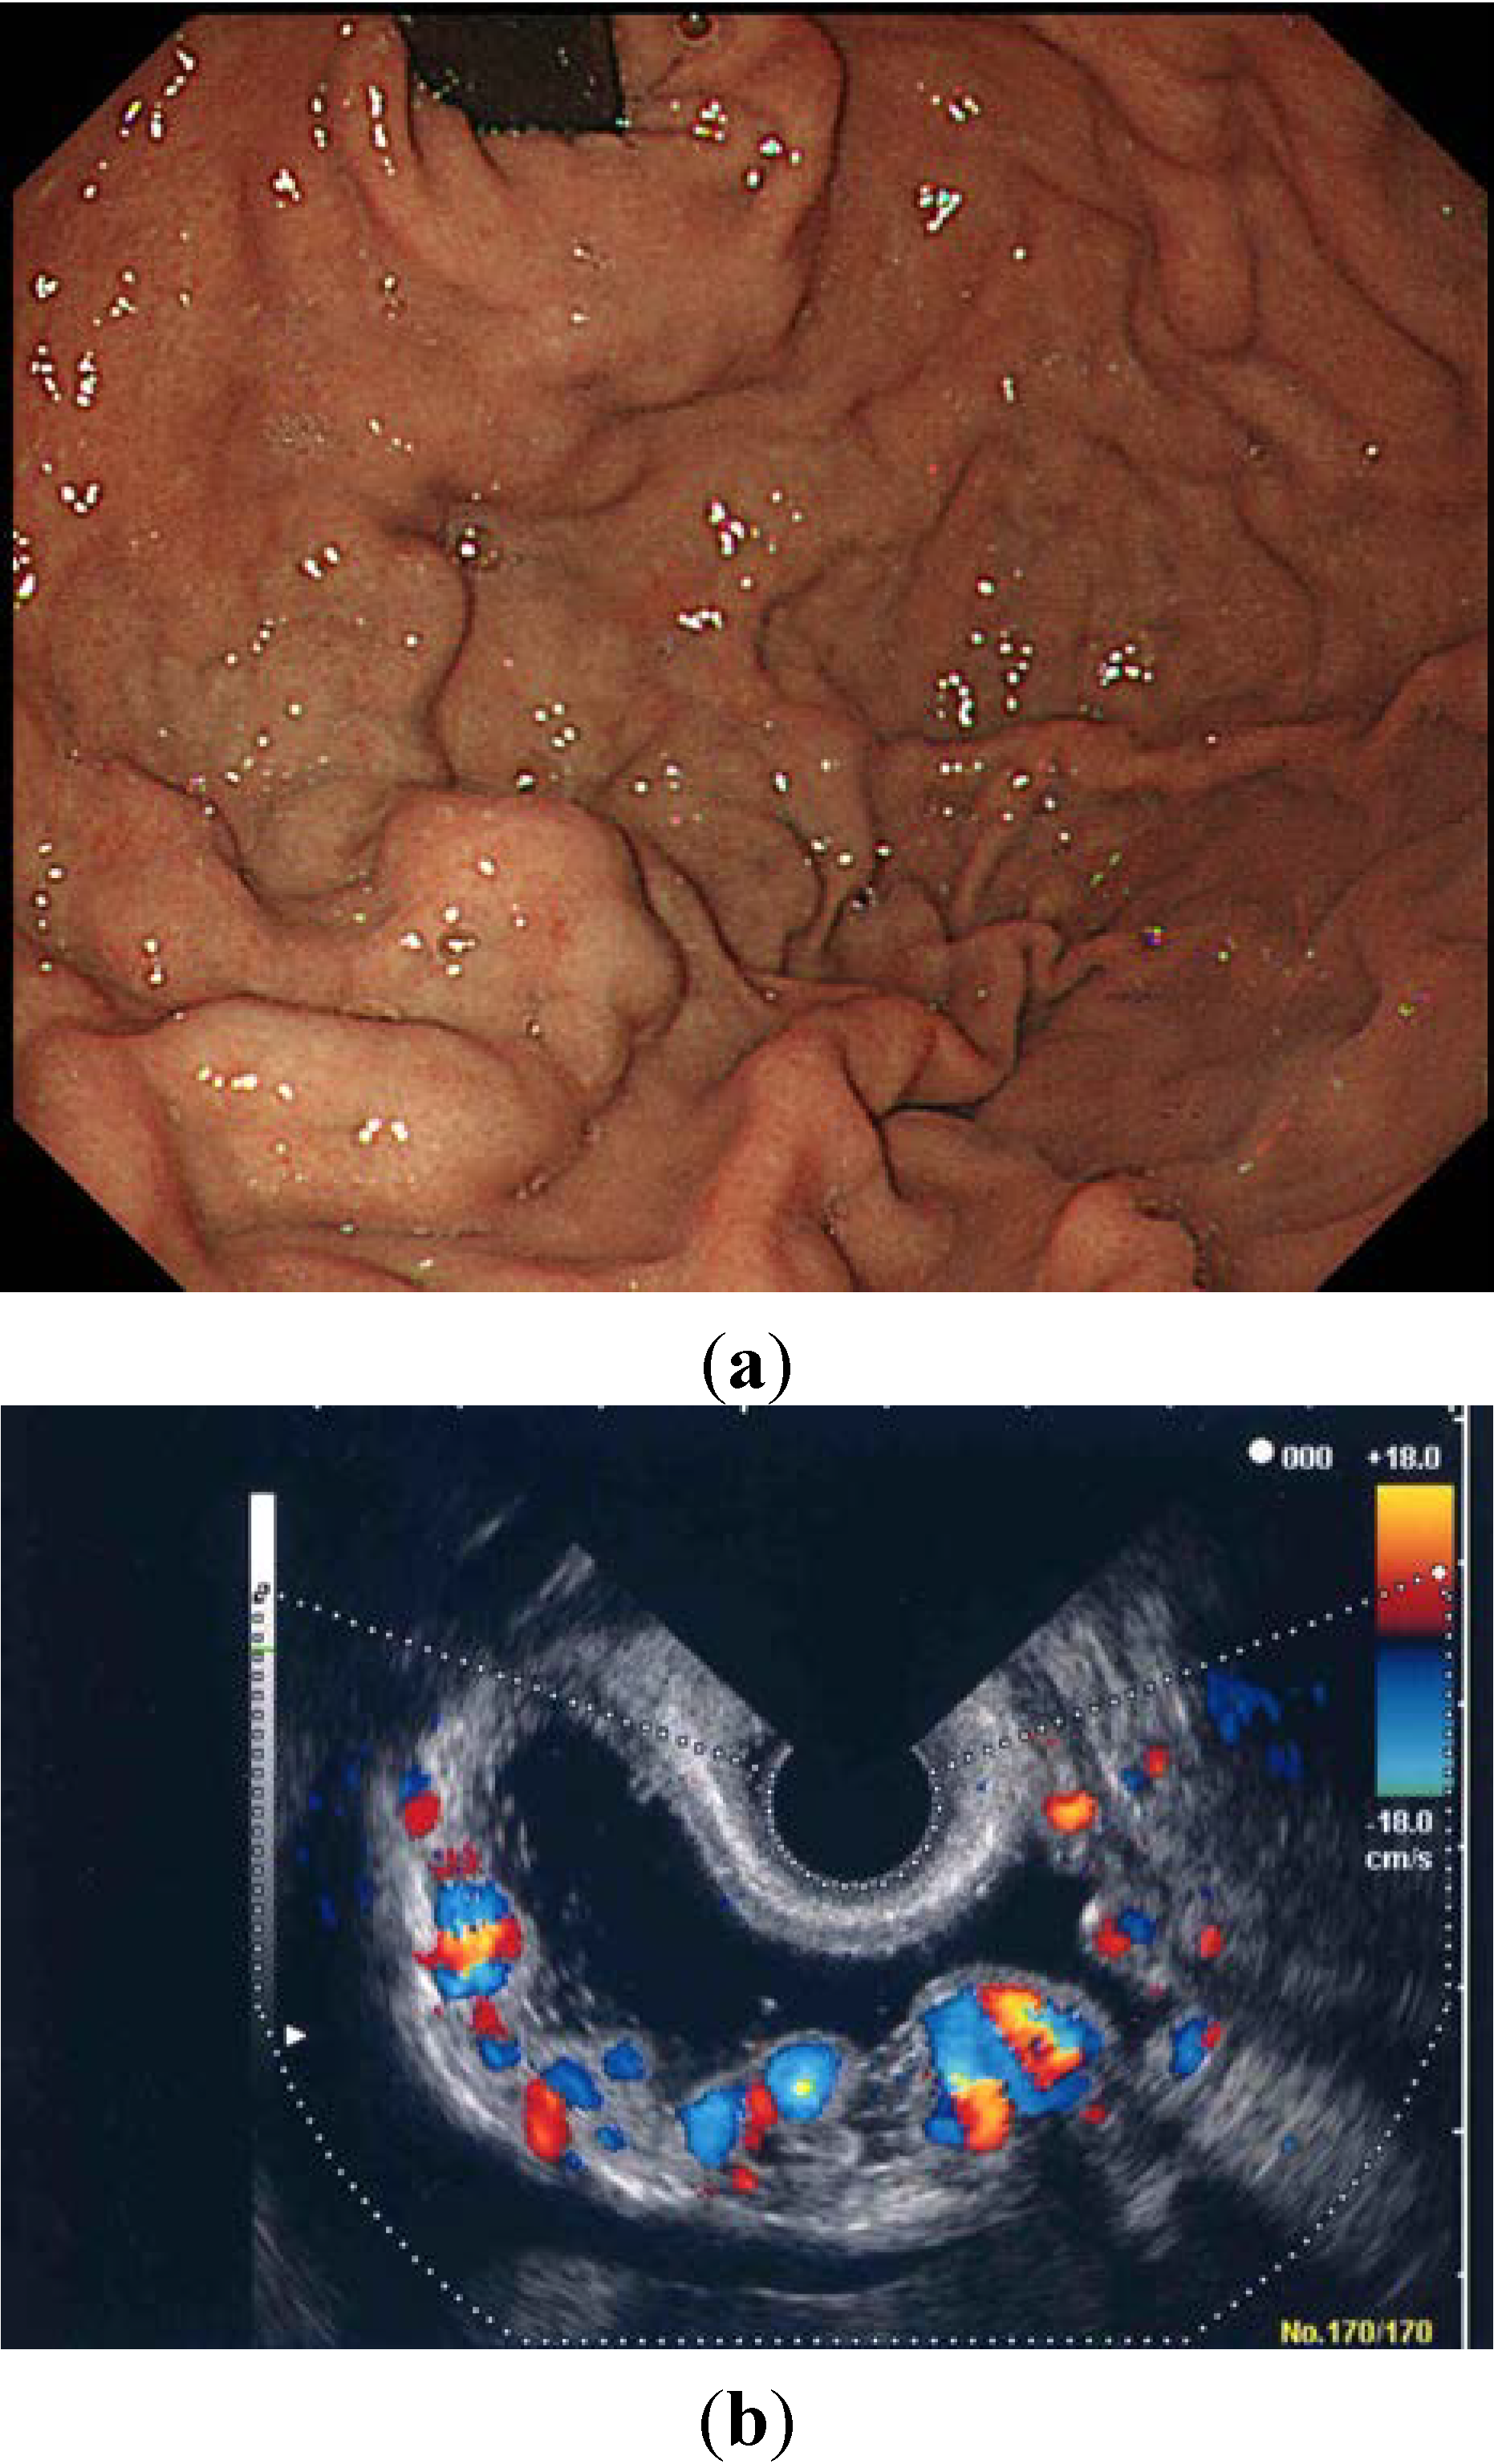

Using ECDUS color flow imaging, gastric varices were delineated in all 16 patients. FFT analysis of variceal blood flow showed a continuous wave in all 16 patients, with flow velocities in the gastric varices ranging between 8.6 and 28.6 cm/s (mean 17.1 ± 4.9 cm/s). Figure 3 shows an electronic radial-type ECDUS image of large, coil-shaped gastric varices located between the fundus and the curvatura ventriculi major of the gastric body, which flows as a continuous wave. Endoscopic findings showed enlarged tortuous, erosion-positive gastric varices in a round fundal region with the pancreatic cancer (Figure 4a). In this case, ECDUS demonstrated clearly gastric variceal color flow images of the round fundal region at the center that expand to the curvatura ventriculi major of the gastric body (Figure 4b). All 16 cases diagnosed as gastric varices secondary to splenic vein occlusion showed similar specific findings on ECDUS color flow images. The ECDUS color flow images of gastric variceal flow depicted specific findings of gastric varices secondary to splenic vein occlusion at the round fundal region at the center, with varices expanding to the curvatura ventriculi major of the gastric body.

Figure 4.

(a) Endoscopic findings showing enlarged tortuous, erosion-positive gastric varices in the round fundal region at the center; (b) Color flow images from endoscopic color Doppler ultrasonography showing a round fundal region at the center, with varices expanding to the curvatura ventriculi major of the gastric body.